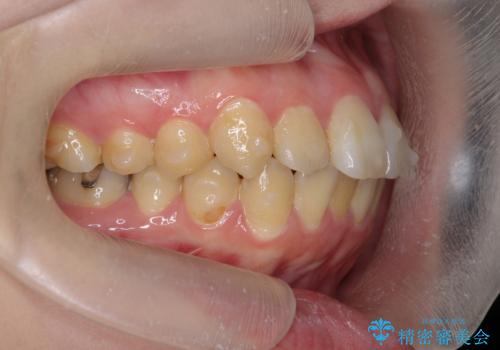

歯を抜かずに行う前歯の角度の改善

- 歯を抜かずに前歯の角度を改善したい、と矯正治療を希望され来院されました。

可及的に前歯部にIPR(歯間の削合)を行い、抜歯をせずマウスピース矯正システムインビザラインで歯の排列を行っていく治療計画としました。

治療の前後を比べると、がたつきや歯の角度が改善したことがしっかりと確認されました。